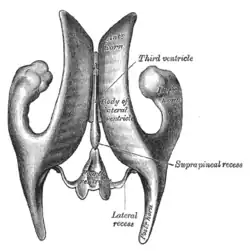

- deux ventricules latéraux, droit (situé dans l'hémisphère cérébral droit) et gauche (situé dans l'hémisphère cérébral gauche) : en forme de fer à cheval, ils sont constitués de trois cornes – frontale (antérieure), occipitale (postérieure) et temporale (inférieure) – se réunissant au niveau de l'atrium (ou carrefour) situé derrière le thalamus[2] ;

- le troisième ventricule (situé dans le diencéphale) : cavité étroite entre les thalamus, elle présente trois étages, thalamique, sous-thalamique et infundibulo-tubérien[3] ;

Les ventricules communiquent entre eux :

- entre les ventricules latéraux et le troisième ventricule : les foramens interventriculaires (ou trous de Monro) ;